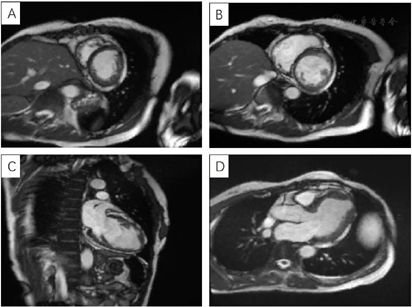

心脏超声提示左室偏大、左室壁不增厚且心肌厚度不均匀,心尖处最薄,部分区域心肌组织较疏松,心肌收缩功能减低;CMR提示左室前壁及心尖处较薄,心内膜下可见片状延迟强化,考虑非缺血性心肌病(心肌致密化不全)。

(1)外院心电图示:室性心动过速、ST-T改变(图1)。(2)外院动态心电图之一(1996年6月4日):平均心率77次/min,最快129次/min,最慢56次/min;见个别室早<64次;"RonT"、"插入性室早"、"室早成对"、"室性心动过速"等均系伪差干扰电脑误判,无ST-T改变(监护23 h)。(3)外院动态心电图之二(2019年8月6日):平均心率64次/min,最快94次/min,最慢52次/min;室性早搏936次,有1次成对室早,49阵室性二联律,无室性心动过速;房性早搏9个(4)上海交通大学医学院附属瑞金医院心电图(图2):QRS时限短,T波低平,I、avL肢导低电压。(5)胸X线:两肺纹理略多,未见确切活动性病变。(6)超声心动图(图3):心腔大小及厚度:左房内径33 mm,左室舒张末期内径52 mm,左室收缩末期内径41 mm,室间隔厚度6.5 mm,左室后壁厚度7.5 mm。二维:左室偏大,左室壁不增厚且心肌厚度不均匀,心尖处最薄,部分区域心肌组织较疏松。静息状态下左室壁各节段收缩活动减低,尤以心尖部最明显。各心瓣膜未见明显增厚,开放不受限。右室壁未见明显变薄。左心功能测定:左室舒张末期容量118 ml,左室收缩末期容量63 ml,左室射血分数46%,左室短轴缩短率23%,每搏输出量55 ml。结论:左室壁心肌厚度不均匀,心尖处较薄,部分区域心肌组织较疏松,综合考虑心肌病可能较大。(7)为进一步明确病因,完善冠状动脉造影,结果提示大致正常(图4)。(8)CMR:左室壁心肌厚度不均,左室前壁及心尖处较薄,增强后左室前壁心内膜下可见片状强化,未见反常运动和矛盾运动,左室射血分数41%。结论:左室壁心肌厚度不均匀,左室功能不全,提示非缺血性心肌病变(心肌致密化不全可能,图5)。

患者亚急性起病,进行性加重,以心悸胸闷为主要表现,每次发作持续时间1~2 h不等,心电图确诊为室性心动过速,心脏超声提示器质性心脏病(心肌病可能),冠状动脉造影排除缺血性原因,最后根据CMR证实,诊断:室性心动过速;心肌致密化不全;慢性心力衰竭(HFrEF,C期,NYHA II级)。

患者中年女性,发作性心悸胸闷9个月余入院。共发生过3次室性心动过速,且每次均在情绪紧张激动时发生,持续时间在1~2 h,发作时以心悸为主,可自主活动,无晕厥黑朦,多可自行转为窦律。入院后心悸胸闷时回顾心电监护可见插入性多源室早,未见室性心动过速发作,完善冠状动脉造影排除冠状动脉粥样硬化性心脏病;心脏超声提示左室壁心肌厚度不均匀,心尖处较薄,部分区域心肌组织较疏松,室性心律失常可能为心肌结构异常所致,后完善CMR提示左室壁心肌厚度不均,左室前壁及心尖处较薄,增强后左室前壁心内膜下可见片状强化,未见反常运动和矛盾运动。左室射血分数41%,结合患者病史,考虑心肌致密化不全可能。与患者及家属沟通后,行单腔ICD植入术(美敦力DVBC3D4)预防心源性猝死,并加用抗心力衰竭口服药物:培哚普利4 mg qd、比索洛尔2.5 mg qd,呋塞米20 mg qd,螺内酯20 mg qd,阿司匹林100 mg qd。